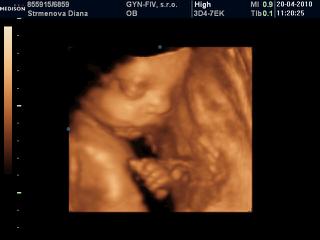

Kamajka tak vidis, nakoniec to ufonik urcite nebude 😉 ja koncim 25tt a zajtra idem na 3D tak aspon uvidis ake foto to budu.

ja som bola na 3D v 22tt a uz maleho bolo krasne vidiet uz bol taky pekny babatkovsky ziadny Ufonik 🙂 ale kedze nechcel ukazat tvaricku tak mi doki v ramci ceny spravi znova 3D na poradni a to budem v 27tt 😉 a moj doktor robi aj take 3D ze vsetko skontroluje pozrie poukazuje da fotku a zaplati sa len 10eur ale je to bez DVD-cka, ale mam stastie ze maly sa nechcel ukazat tak to budem mat zadarmo a aspon ho zase uvidim stuplika maleho ze ako narastol 😵

ahojte...didulka, krasne zabery, mala je nadherna 😵

Didulka kraaaaaaaaaaaaaasa, uz nech je zajtra a ja mam take iste krasne fotecky 😉